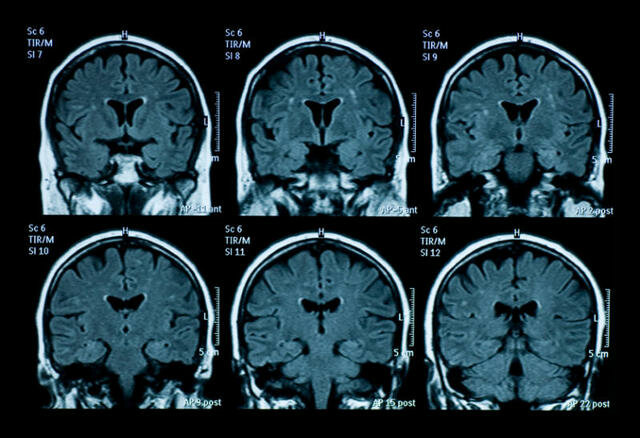

La neuropsicología ha tenido un crecimiento notorio, se considera el área con mayor desarrollo dentro de la psicología y dentro de las neurociencias en general. Encontramos avances como: Surgimiento de las imágenes cerebrales, utilización de pruebas estandarizadas en el diagnóstico, desarrollo del área de la rehabilitación neuropsicológica, profesionalización de la neuropsicología, aumento en el número de publicaciones, integración conceptual, ampliación del campo de trabajo. pág. 26

Se fortalece la investigación con el empleo de imágenes noya anatómicas sino funcionales, en particular la resonancia magnética funcional y la tomografía por emisión de positrones, que han permitido visualizar la actividad cerebral durante la realización de diferentes tareas cognoscitiva como, hablar, leer etc. pág. 27